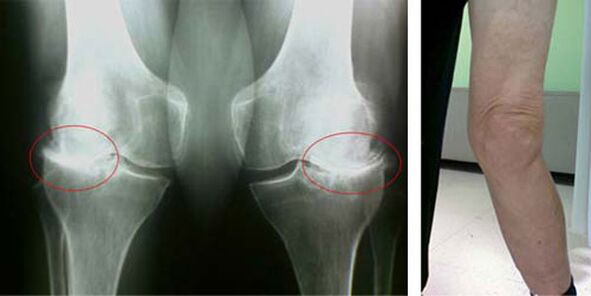

Os estágios iniciais da ocorrência de uma patologia como artrose da articulação do joelho não se manifestam visualmente de forma alguma. No entanto, após um certo tempo, o paciente percebe sinais de deformidade no joelho, bem como uma curvatura característica ao longo do eixo da perna (dirigida para dentro). Há também uma crise quando você precisa dobrar a perna.

A presença de dor, movimento limitado no joelho faz com que a pessoa consulte um médico e faça um exame. Para fazer isso, ele precisa passar por testes e tirar um raio-x da articulação doente. Se essas medidas não forem suficientes para confirmar a artrose da articulação do joelho, a ressonância magnética é realizada. Com base nos dados coletados, o médico escolhe os melhores métodos de tratamento.

radiografia de osteoartrite do joelho